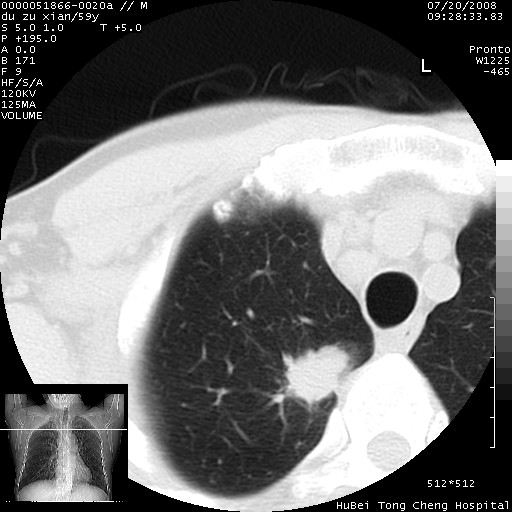

以下是引用宇宙ct在2008-8-25 23:21:00的发言:[br]右肺周围性肺癌并肋骨转移,纵隔淋巴结转移。

以下是引用zsl6918在2008-8-25 22:40:00的发言:[br]右肺周围性肺癌并肋骨转移,纵隔淋巴结转移。

以下是引用zy_zj在2008-8-26 15:24:00的发言:[br]单从病变本身,我倾向良性炎性病变,但肋骨转移了,所以说是考虑右肺周围性肺癌并肋骨、纵隔淋巴结转移可能性大。